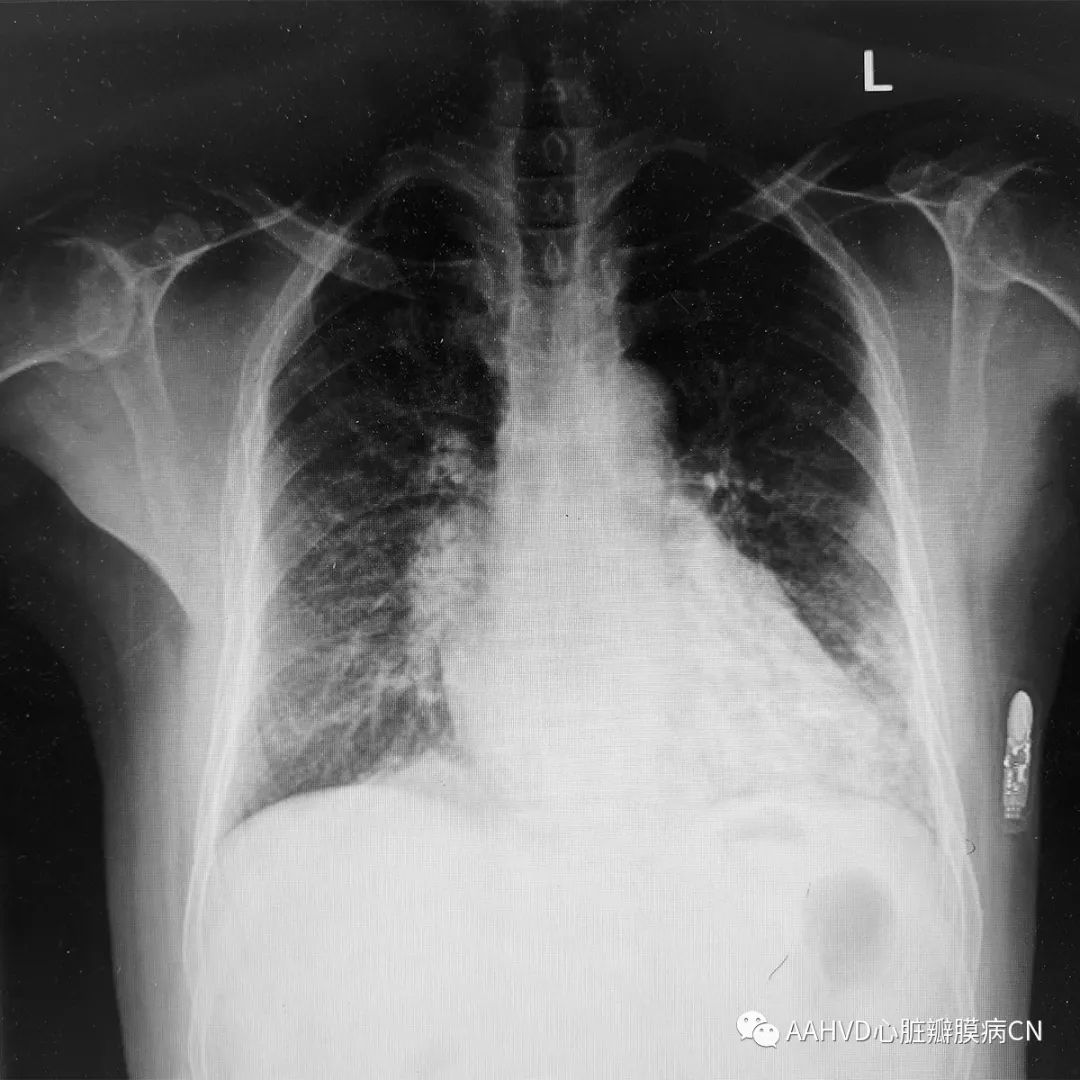

女性,51岁,主诉:胸闷憋气1月余

手术日期:2018年12月12日

术前胸片

术前经胸超声:

风湿性心脏病,二尖瓣返流面积14.1cm²(重度返流),瓣口面积1.4cm²(重度狭窄),前向流速196cm/s,三尖瓣返流面积8.1cm²(中度返流)。室间隔基底段增厚(12cm)。